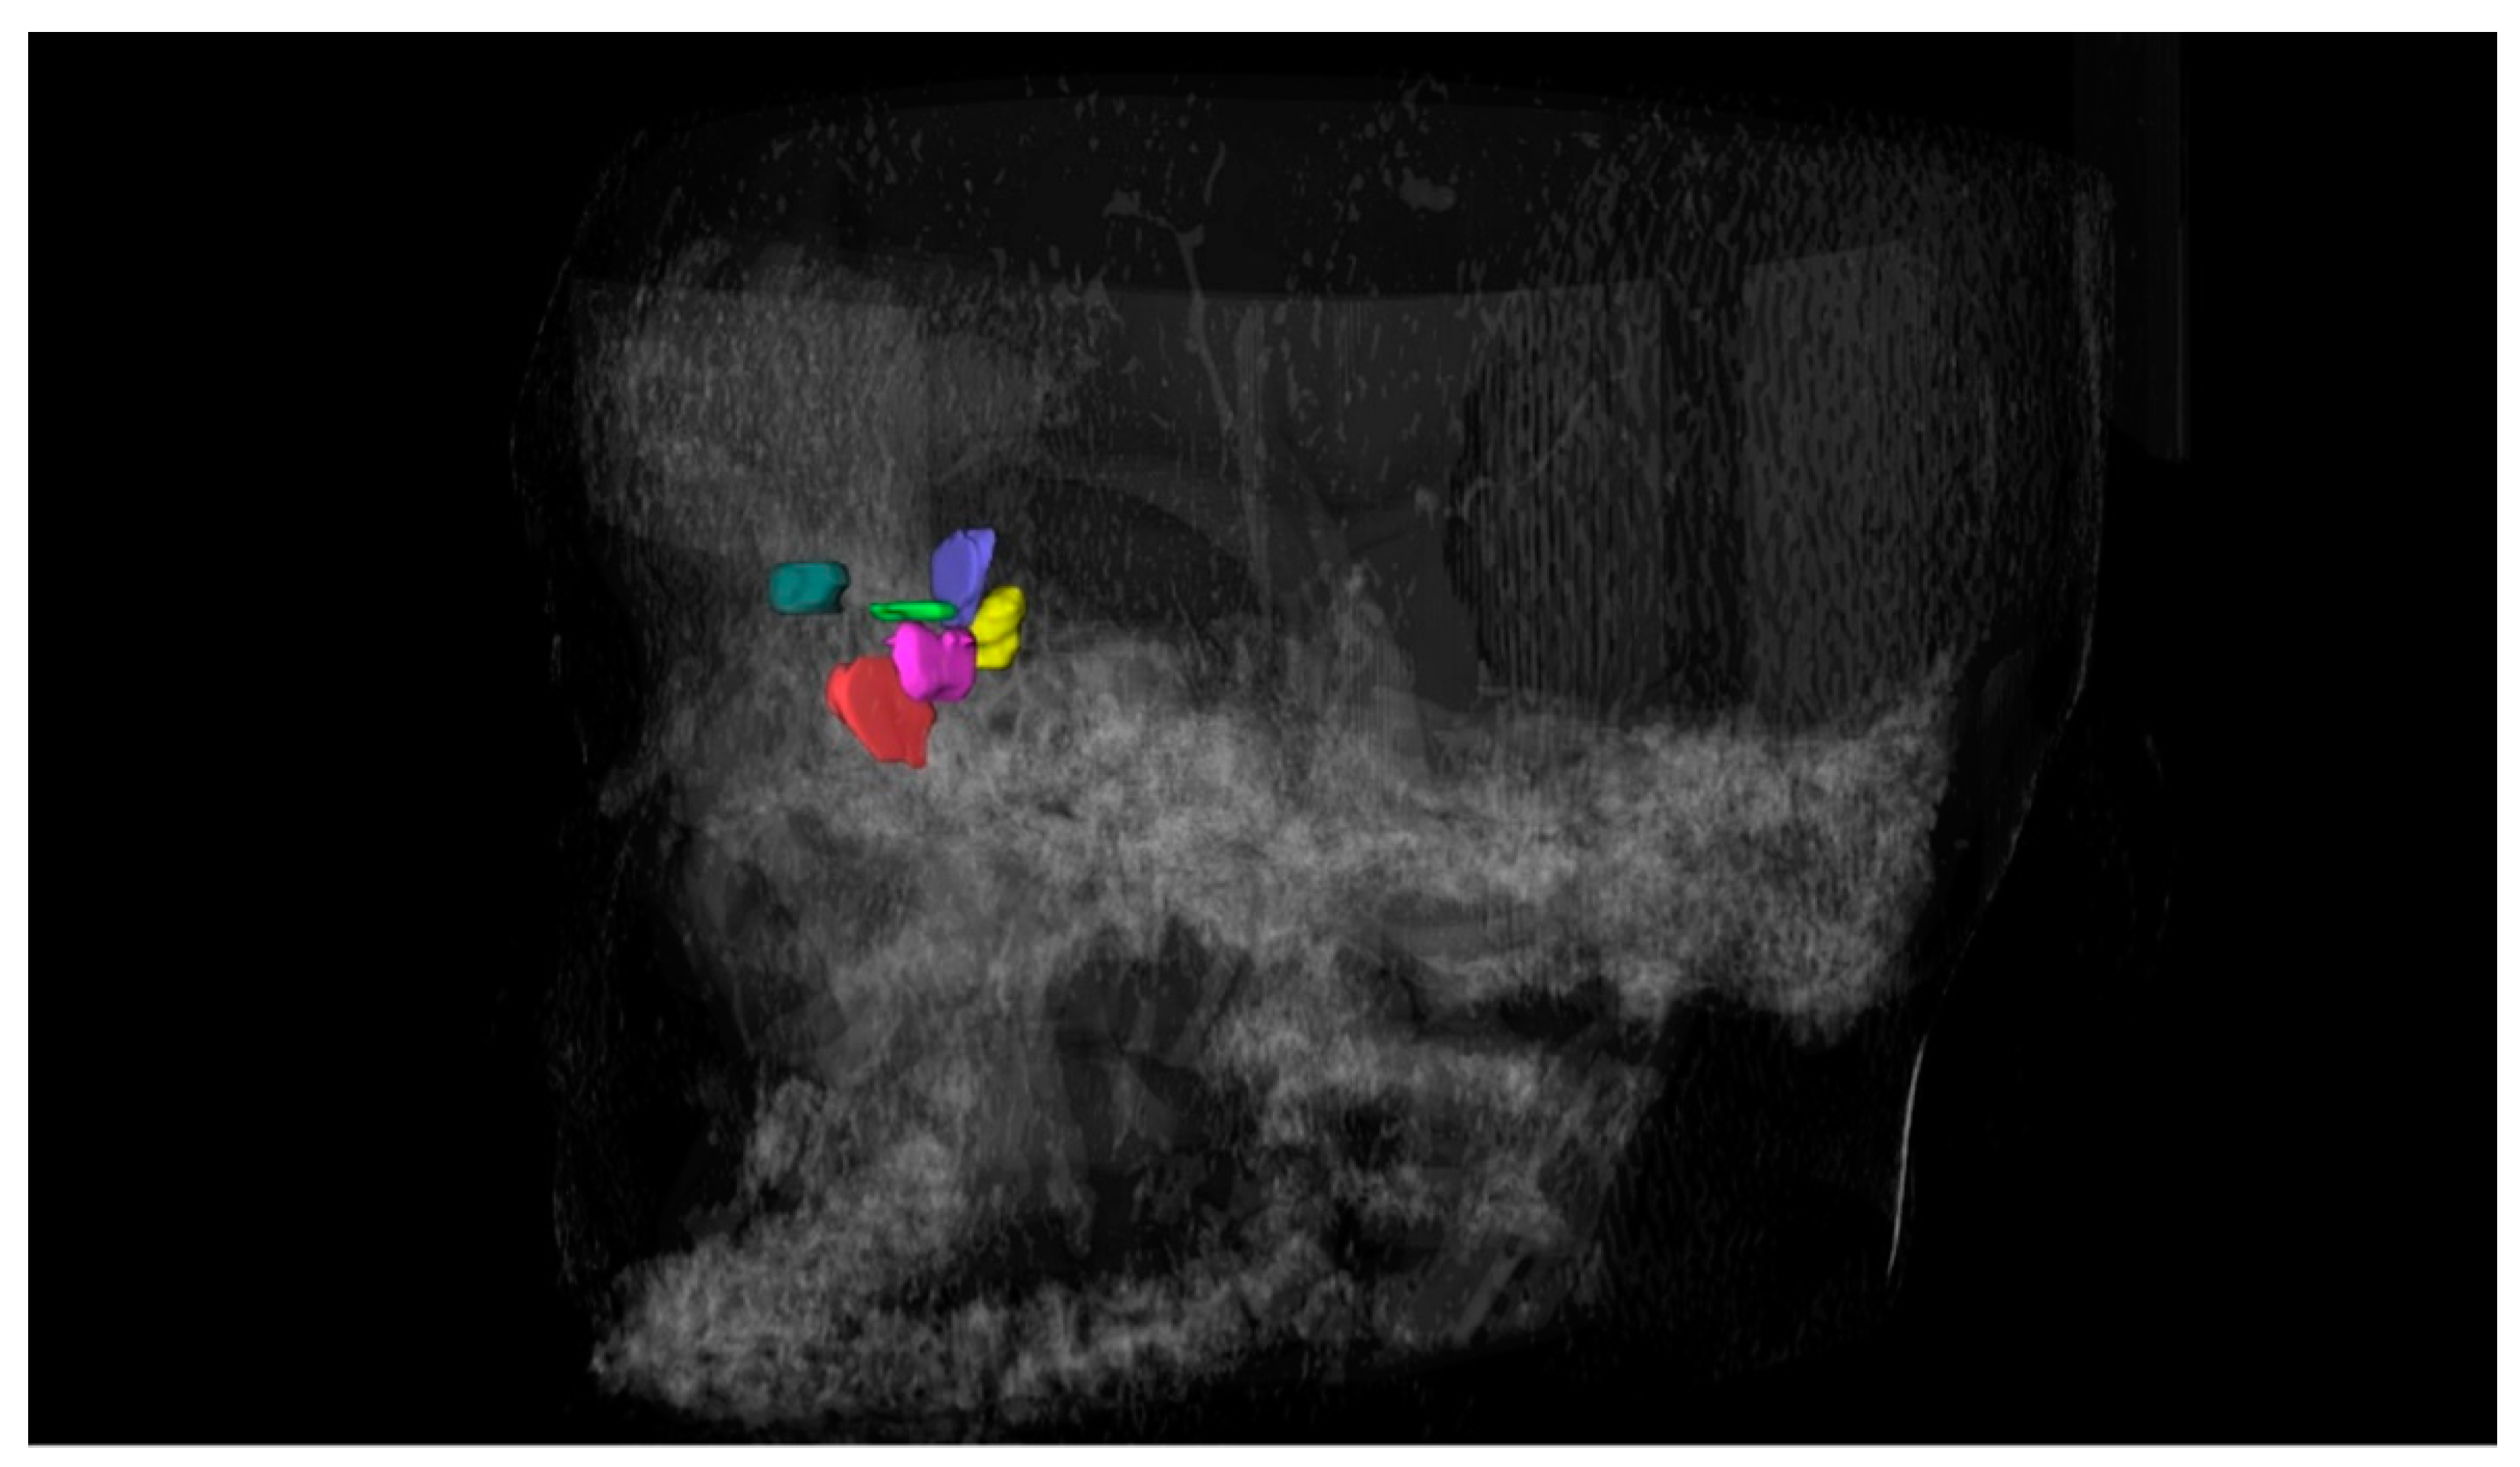

2.2. Identification and Data Extraction

2.3. Critical Data Analysis

3.1. Agger Nasi Cell

3.2. Supra Agger Cell

3.3. Frontal Septal Cell